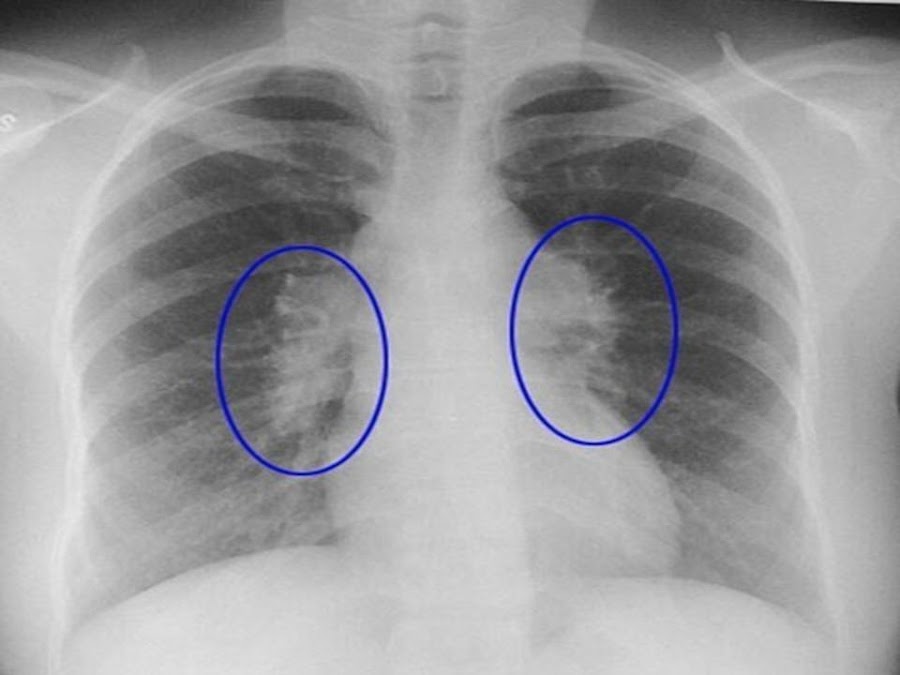

Las adenopatías son de localización hiliar bilateral (Figura 2) y, con menos frecuencia, paratraqueales derechas y en la ventana aortopulmonar, sin embargo, la adenopatía unilateral es excepcional y obliga a considerar otros diagnósticos, tales como tumores, linfomas, micosis profundas o tuberculosis.

Figura 2.- RX de tórax con adenopatías hiliares bilaterales.